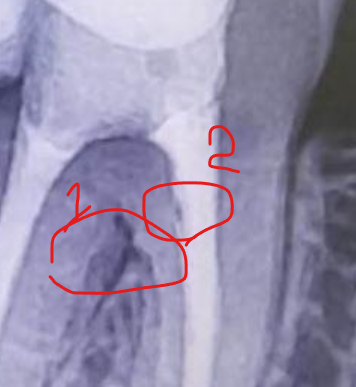

Aleksandr21321 Опубликовано 29 декабря, 2023 Автор Поделиться Опубликовано 29 декабря, 2023 27.12.2023 в 11:43, Notherbrick сказал: Такое количество материала за верхушкой в целом не критично. Но есть вторичный кариес и, возможно, трещина в районе бифуркации корней. Нужно КТ чтобы выяснить наверняка. А под трещиной вы имели в виду 1 или 2? Ссылка на комментарий

Notherbrick Опубликовано 29 декабря, 2023 Поделиться Опубликовано 29 декабря, 2023 1 подозрения там Ссылка на комментарий

Aleksandr21321 Опубликовано 29 декабря, 2023 Автор Поделиться Опубликовано 29 декабря, 2023 (изменено) 14 минут назад, Notherbrick сказал: 1 подозрения там а это вина матушки природы или врача? просто это уже за пределами зуба проблемы, тут наверное винить стоматолога не нужно? кстати, а почему эта трещина сама не зарастет? Изменено 29 декабря, 2023 пользователем Aleksandr21321 Ссылка на комментарий

Notherbrick Опубликовано 29 декабря, 2023 Поделиться Опубликовано 29 декабря, 2023 Зуб был сильно разрушен и не выдержал нагрузки. Ссылка на комментарий